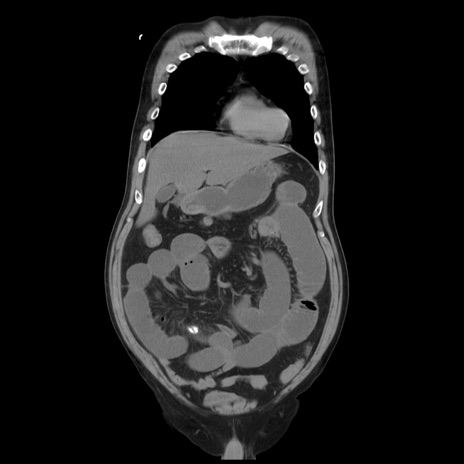

横断像

【症例】 60歳代男性

【主訴】 腹部膨満、嘔吐

【現病歴】5日前頃より倦怠感を認め食事量減少し4日前の朝嘔吐、食事摂取困難となった。 3日前近医受診し点滴施行され整腸剤などを処方された。 当日他院を受診し、腹部膨満著明、炎症反応の上昇(CRP10.8、WBC11200)あり、紹介受診となる。

【身体所見】 意識JCS1 受け答えがはっきりしないBP 111/57mHg、 P 67bpm、、BT35.2°C、SpO2 97%(RA)、 腹部:膨隆、打診で鼓音あり、全体的に圧痛有り、腸蠕動音(-)、反跳痛ははっきりせず。

【データ】WBC 11400、CRP 14.20